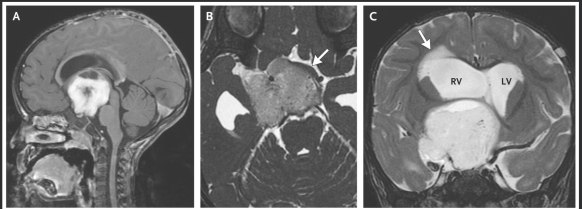

In essence, a 19 month girl with good linear growth had stopped gaining weight around 7 months of age. After exhaustive evaluation, detailed in this report, the patient had an MRI which revealed a brain tumor and she was diagnosed with diencephalic syndrome. Key features include good appetite/caloric intake, happy appearance, and cachexia.

In many cases of diencephalic syndrome, symptoms like vomiting may be present on an intermittent basis as well as nystagmus or strabismus; these symptoms develop due to obstructive hydrocephalus.